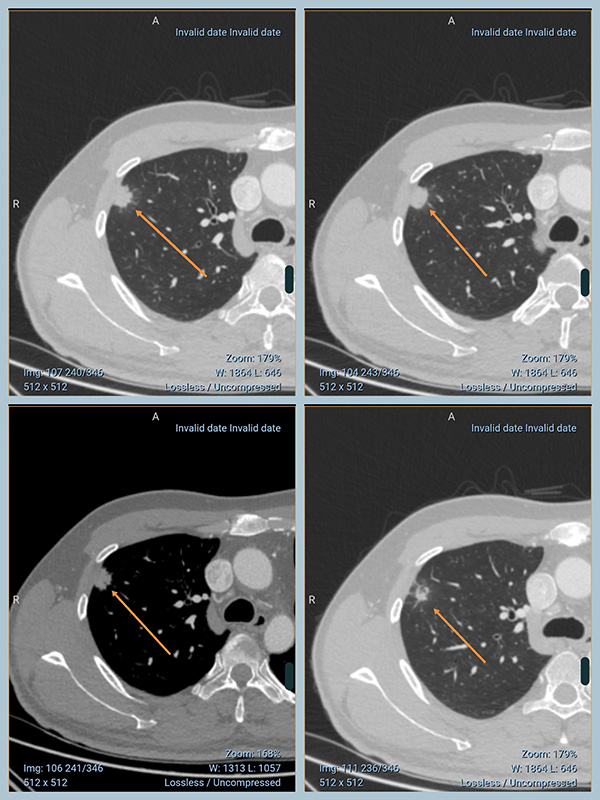

30多岁年轻患者,2026年2月CT检查发现:

“右肺上叶前段实性结节,大小1.6cm,有分叶,边缘有短毛刺,邻近胸膜有牵拉、增厚,内部可见空泡。增强轻度强化,恶性可能大。建议穿刺活检。”

实性、分叶、毛刺、胸膜牵拉、空泡,这些组合在一起是典型恶性特征。

他把第一次的CT发了过来

两次CT对比,变化(缩小吸收)一目了然!